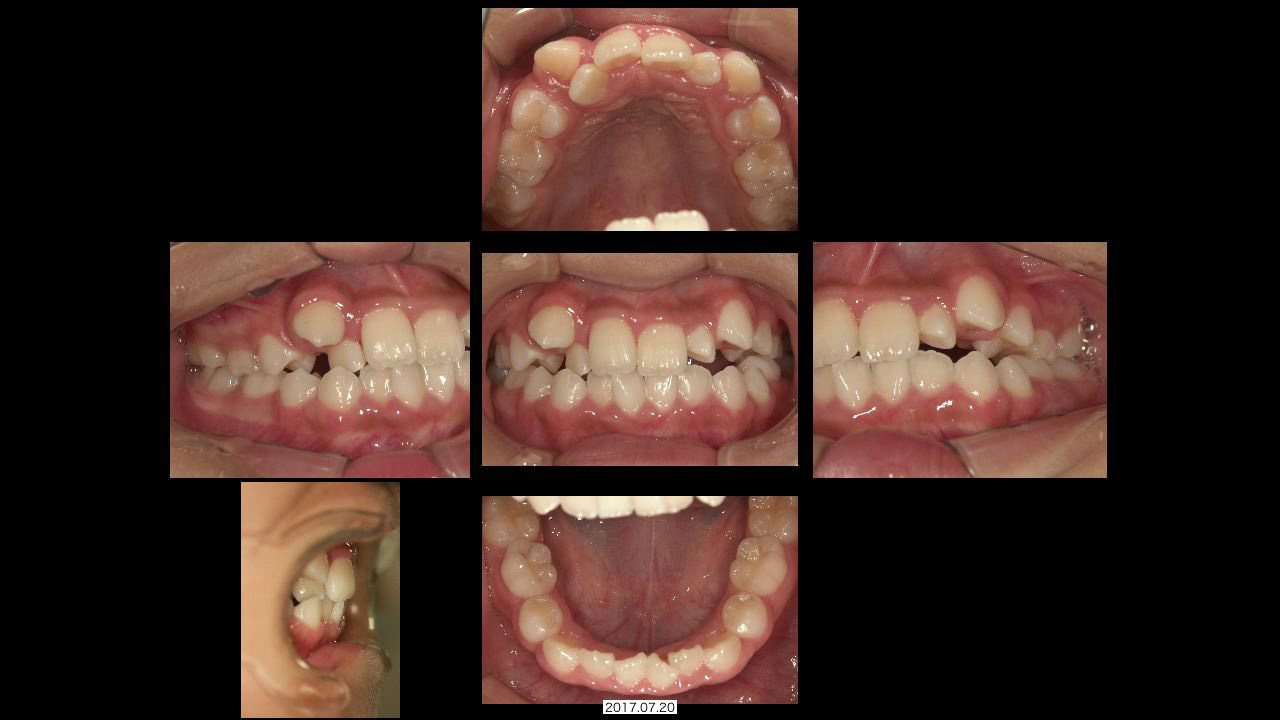

小学生になると乳歯から永久歯に生え変わりが始まります。前歯が生え変わっていくときに、きれいに並ばなくてガタガタになってしまったり、明らかに永久歯が生えるスペースが足りなかったりする子どもたちが増えています。

成長の状態によっていくつかの治療方法があります。成長期の子どもの歯並びが気になる、鼻が詰まっている、口が開いていることが多いなど、子どもさんの状態で気になることがあればお気軽にご相談ください。